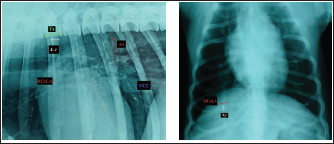

In each objective methods of cardiac silhouette measurement, the LA and SA were measured in the same way. In LL radiographs, cardiac LA length (mm) was the line extending from the ventral border of the left mainstem bronchus to the most distant ventral contour of the cardiac apex. SA length (mm) was the line drawn perpendicular to the cardiac LA on the widest part of the cardiac silhouette. In DV radiographs, the LA was drawn as the line starting from the dorsal margin of the right atrium projection to the left apex. The SA was drawn perpendicular to the LA at the widest part of the cardiac silhouette (Fig. 1A and B).

Fig. 1. A and B. Measurements of LA and SA in LL (A) and DV (B) views, with marked T4, S4, M, TI length: LA – long axis, SA – short axis, T4 - the length (mm) of the body and caudal disc of the T4vertebra, S4 - the length (mm) of the S4, M – the length (mm) of the M, TI - the length (mm) of a dog’s TI.